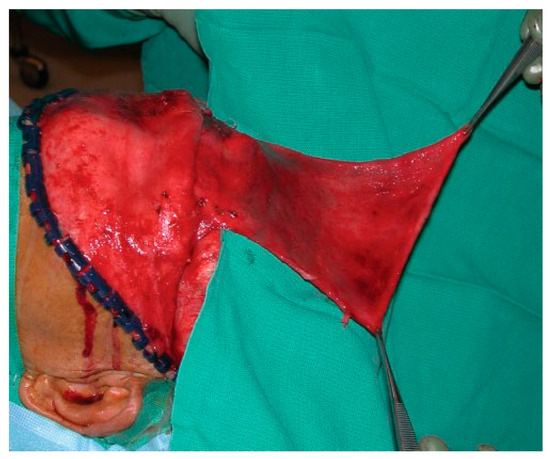

Figure 16.

Intraoperative photo of a large pericranial flap.